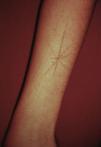

Excoriations. Excoriations are the most easily diagnosed factitious lesions. They are usually linear (Fig. 2) and are most often inflicted using the fingernails (Fig. 3) although a variety of sharp objects may also be used (Fig. 4). Distinguishing between DA and neurotic excoriations can sometimes be difficult, but patients who have the latter condition recognize that they have caused the lesions. Excoriations are highly susceptible to infection and an indicative finding is the absence of itching before the onset of the lesion.26

Excoriations are a common clinical form of DA because the lesions are easy to inflict; in our case series they were observed in 52 (25.8%) of 201 patients and were more common in women (28.4%) than in men (17.7%).